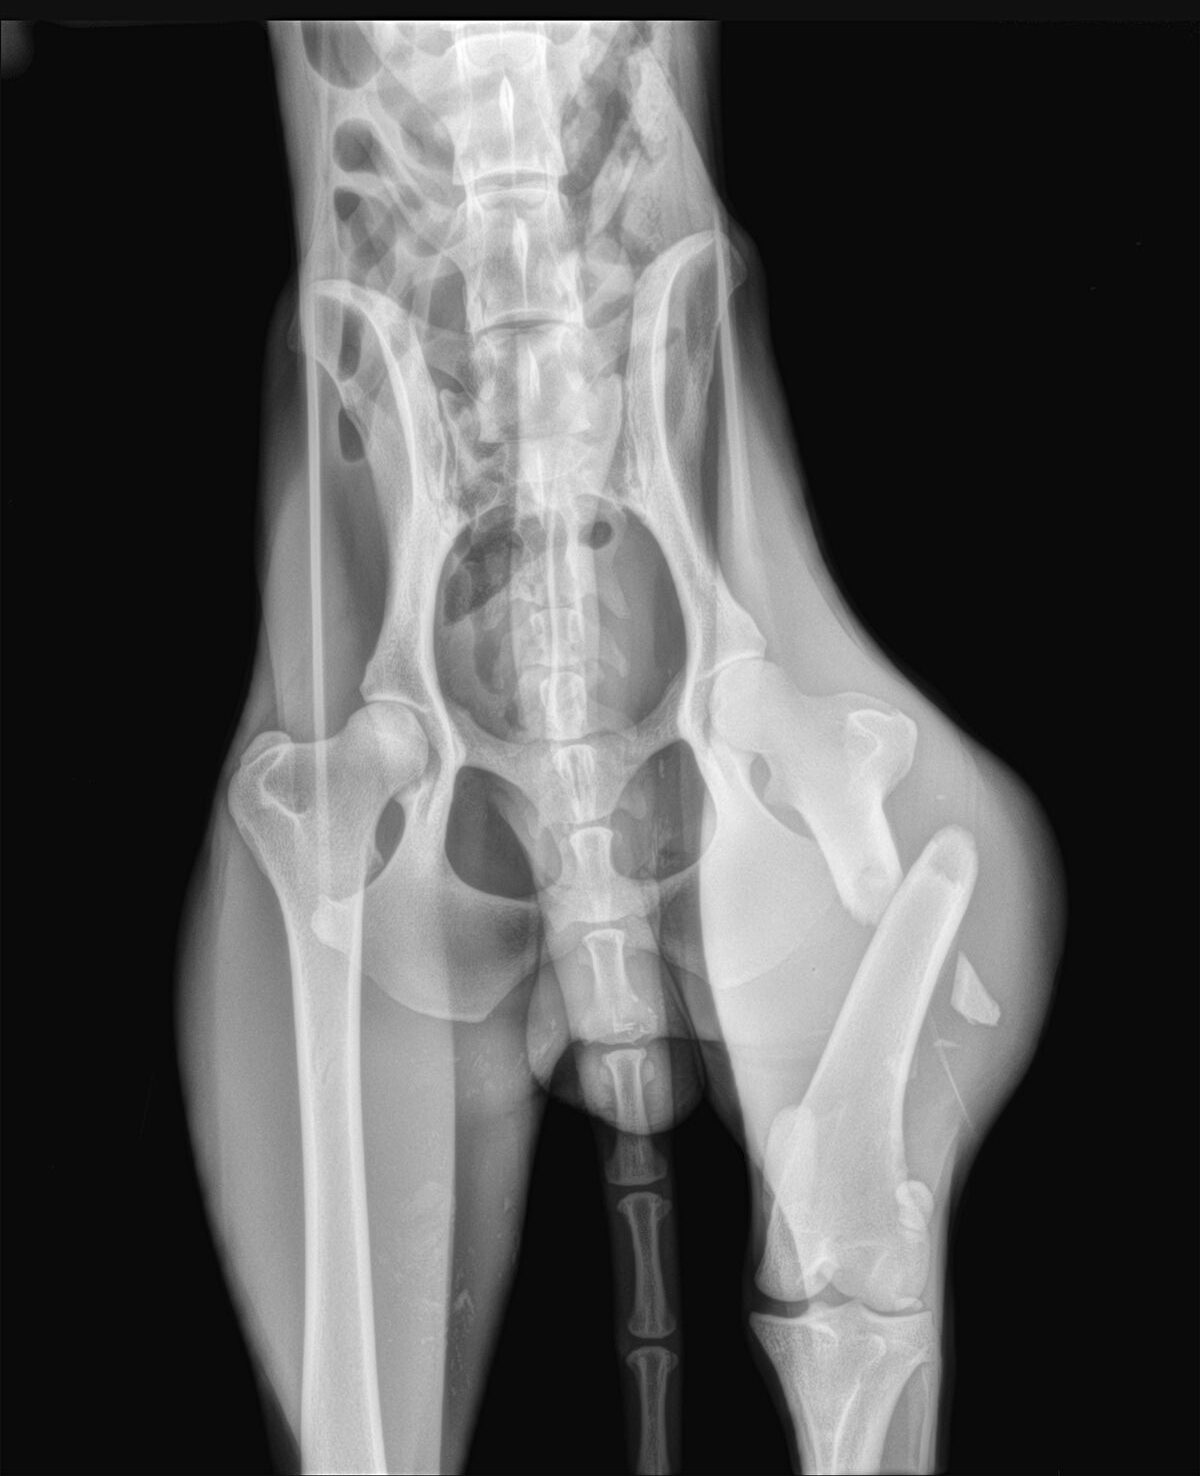

Marcus n’était plus qu’un véritable squelette, avec une fracture complexe du fémur au postérieur gauche. Il a dû vivre un véritable enfer, seul, blessé et affamé…

Il a été opéré en urgence à la clinique du refuge de la FBM, où il est actuellement en convalescence 🩺. La clinique est aujourd’hui totalement saturée, faisant face chaque jour à l’arrivée de nouveaux cas lourds : fractures, blessures graves, chiens brisés par la maltraitance et l’abandon… 😞 Malgré cette situation extrêmement difficile, Marcus a pu être pris en charge et bénéficie désormais de tous les soins nécessaires.